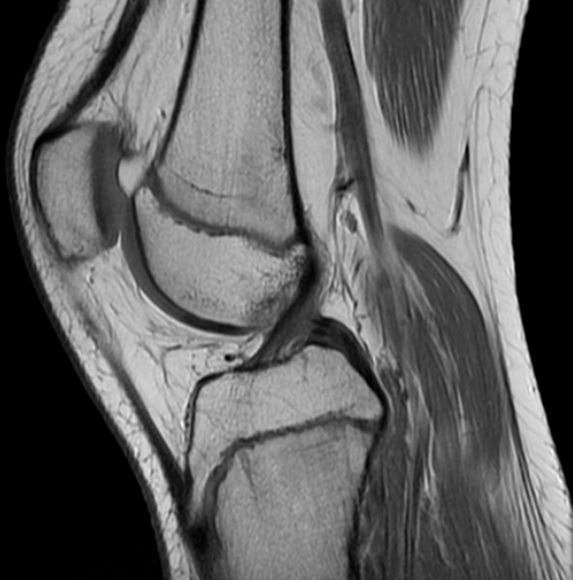

Biomechanical insights to prevent and treat kneecap instability

Patellar instability, a condition associated with partial or full dislocation of the kneecap (patella), is common among adolescent athletes and can significantly impact mobility and long-term joint health. Using magnetic resonance images and techniques in statistical shape modeling, this research aims to identify the anatomical and biomechanical factors that contribute to patellar instability, with the goal of guiding personalized treatment and improving outcomes. Through this work, we aim to influence clinical decision-making and enhance injury prevention and treatment.

​This research is conducted in collaboration with orthopaedic surgeons at Hospital for Special Surgery, Cincinnati Children's Hospital Medical Center, and Stanford Medicine.